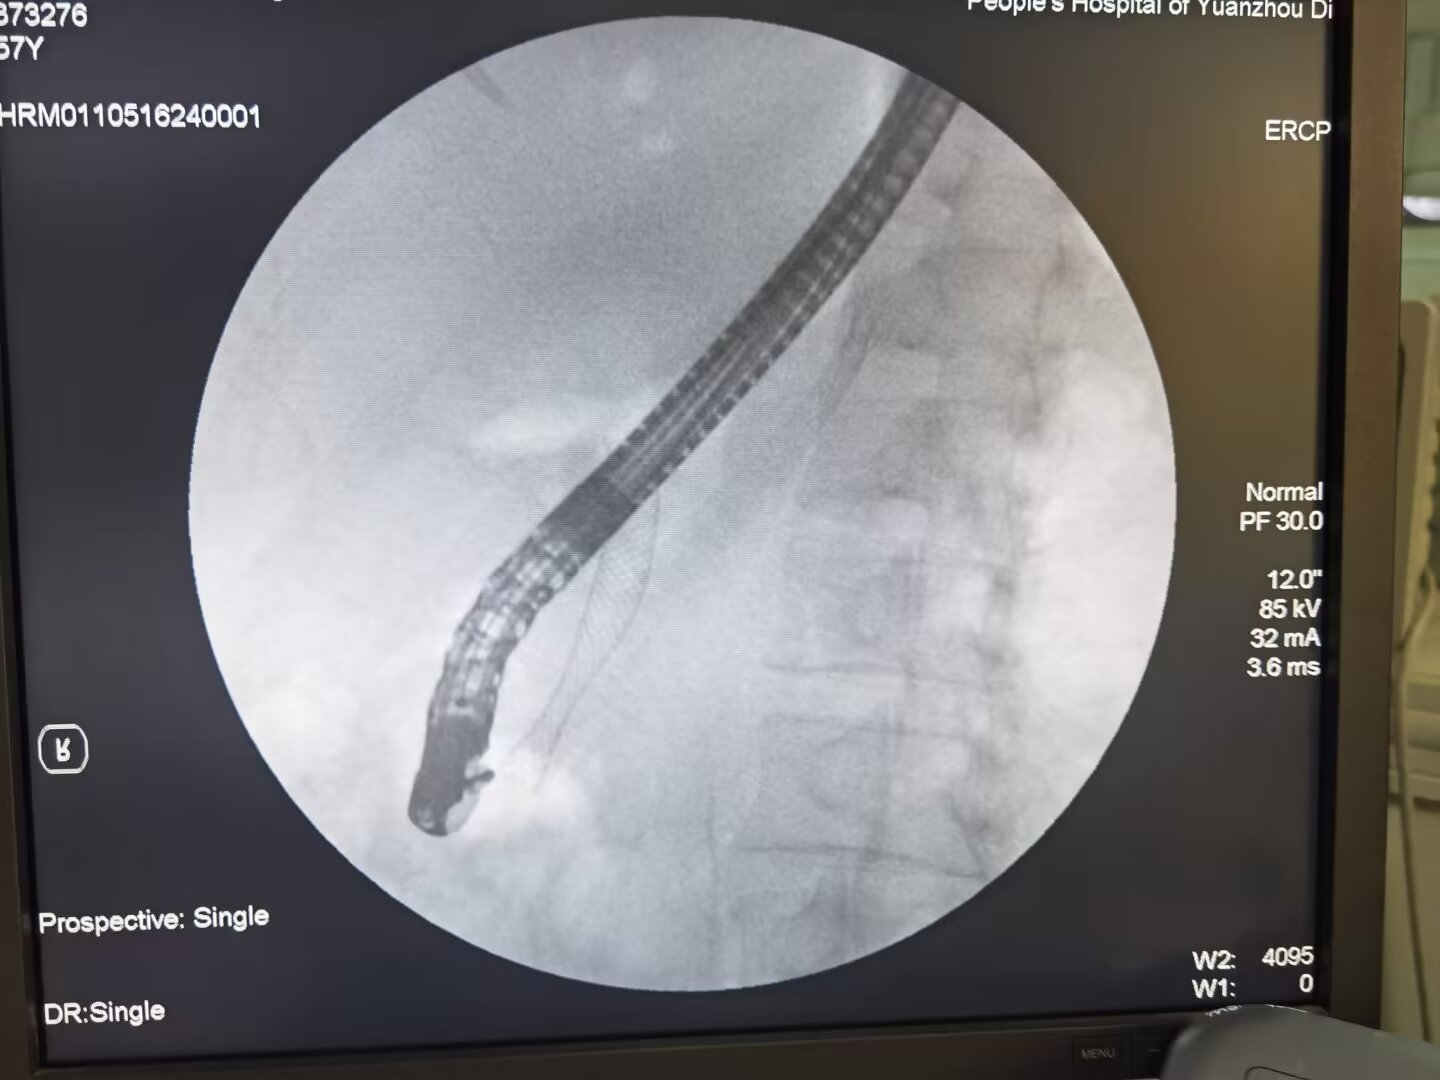

消化内科包括消化、血液、是市级重点专科,科室拥有奥林巴斯电子胃肠镜,日本东芝数字化摄影X线机等国内最先进医疗设备。现有医务人员28名,其中主任医师2名,主治医师3名,主管护师4名,现有床位52张。多年来在上海长海医院,福建附属第一人民医院,宁夏医科大学附属医院,自治区人民医院,银川市第一人民医院等医院的大力帮扶下,成长了一批技术过硬的医疗队伍,在上消化道出血,肝硬化,消化性溃疡,炎症性肠病,急慢性胰腺炎、上消化道早癌,胃肠道肿瘤,胆总管结石,肿瘤等胆胰疾病以及各种贫血性疾病的治疗方面积累了丰富的临床经验。承担了国家胃肠早癌筛查项目,受到了国家表彰,在内镜诊断及治疗方面引领固原市,目前开展的胃肠镜常规检查以及无痛胃肠镜诊治,胶囊内镜检查,小探头超声内镜检查,食管支架置入,结肠支架置入术、十二指肠支架置入术、内镜镜下止血术、胃肠道息肉切除术、肠镜下内痔硬化及套扎术,食管胃底静脉曲张硬化及套扎术(EVS,EVL),空肠管置入术,胃造瘘术,内镜下粘膜切除术(ESD)及内镜下粘膜剥离术(EMR)、胰胆管逆行造影(ERCP)及取石术等内镜诊治新技术。